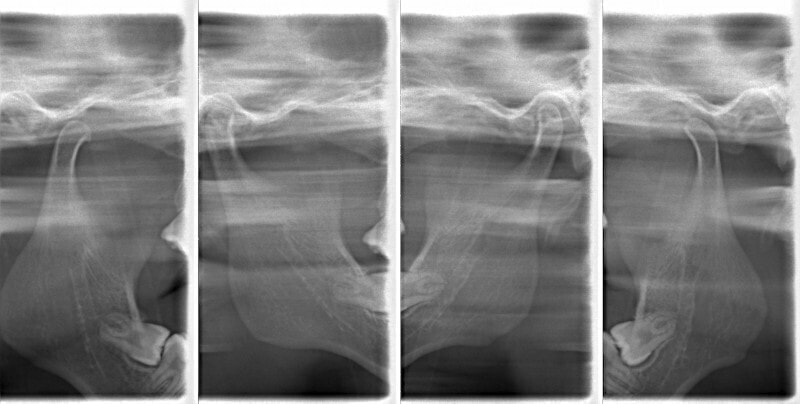

検査時のセファロ分析側貌

上顎劣成長の値が出ています。顔面、下顎骨骨体自体は標準偏差1S.D.内に収まっています。

顔面と顎骨の幅径はある程度確保されているので、非抜歯が可能であると診断しました。

やはり統計通り、左上3番の埋伏です。

左上2番の歯根吸収が認められますが、保存不可能なレベルではありません。

成人の反対咬合なので、少し顎関節にダメージはありますが、重症ではありません。

治療中のレントゲンです。

7番、8番の状態や歯根のパラレリング(平行性)をチェックしています。

左上2番の歯根の状態もなんとかもちそうです。

上顎劣成長症例ですが、鼻腔の状態も悪くありません。

治療後のセファロ分析です。

反対咬合の治療は、FX(フェイシャルアキシス)が開きやすいのですが、治療後も良好な値を保つことができました。FXがあまり開きすぎると、咬合力が落ちてしまいます。

下顎の右側への偏位は解消されました。

大臼歯は整直されております。

歯根のパラレリングは良好です。

左上2番の歯根も問題なさそうです。

下顎8番は保定期間に入り、しばらくして咬合が安定してから抜歯する予定です。

特に左側の咬合時の顎関節の位置に改善が認められます。